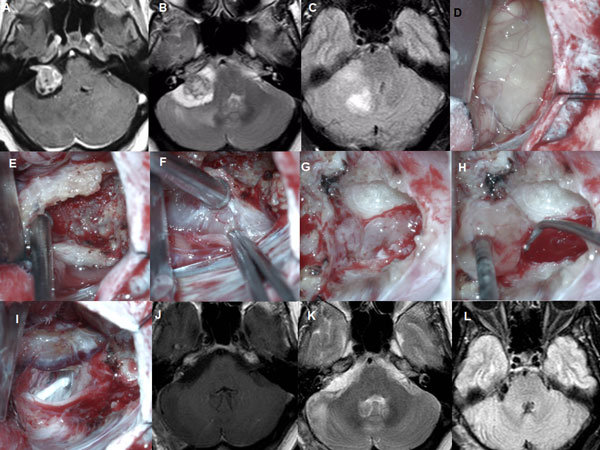

Figura 7: Paciente masculino de 37 años, operado de SV T4b derecho con quiste externo. A-C: RM cerebral preoperatoria. D-J: imágenes intraoperatorias, K-L: RM cerebral postoperatoria

Figura 8: Paciente masculino de 62 años, operado de SV T4b multiquístico. A-B: RM preoperatoria. C-D: RM cerebral postoperatoria.